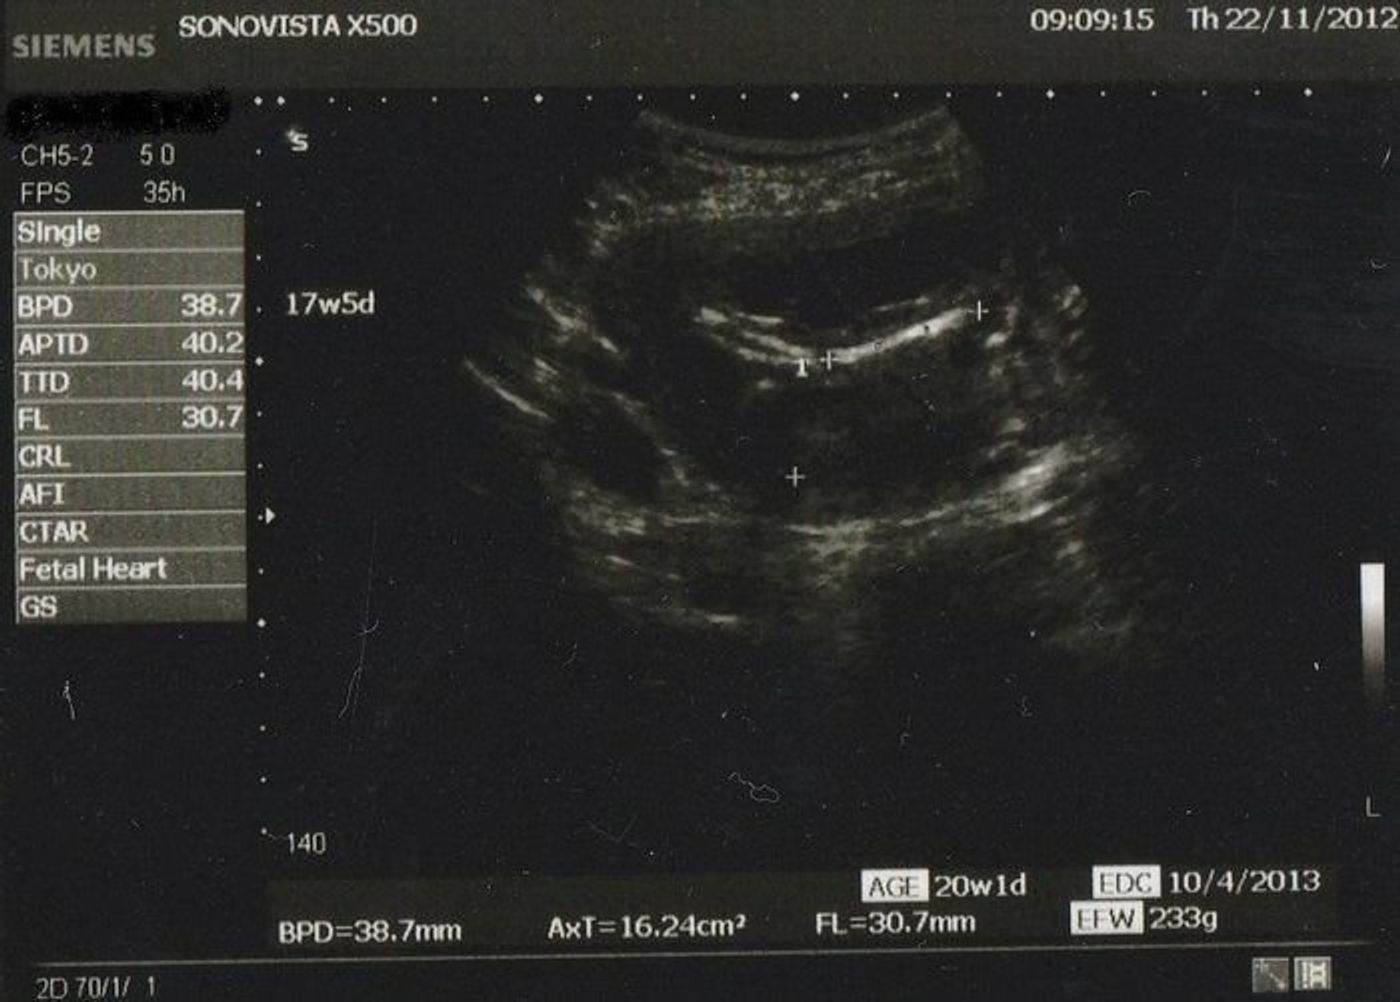

妊娠週 17w5d 検診のたび大きくなっていて、毎月エコーが楽しみです。 今回も元気に動いていました。 写真は横顔です。 お股を見せてくれましたが、まだ性別分かりそうにないとのことで、次回にお預け。 (もしかして女の子? )大きさは約12cm。 双 女の子の性別判定はいつから可能? 女の子の性別判定はいつから可能なのでしょうか? 男の子も女の子も外性器がしっかりと形成され、 性別判定ができるようになってくるのは大体どちらも早くて妊娠16~17週目くらい と言われています。 が、女の子の性別判定は残念ながら男の子に比胎児の性別ですが17週の頃から『たぶん女の子』と言われています。 先週の検診でも『今のところ女の子かな。隠してるかもしれないけど。』と言わ 質問No 17週の女の子のエコーのふくらみ 17週になる2人目妊婦です

![]() 妊娠17週5日 17w5d の超音波 エコー 写真 | ![]() 妊娠17週5日 17w5d の超音波 エコー 写真 | ![]() 妊娠17週5日 17w5d の超音波 エコー 写真 |